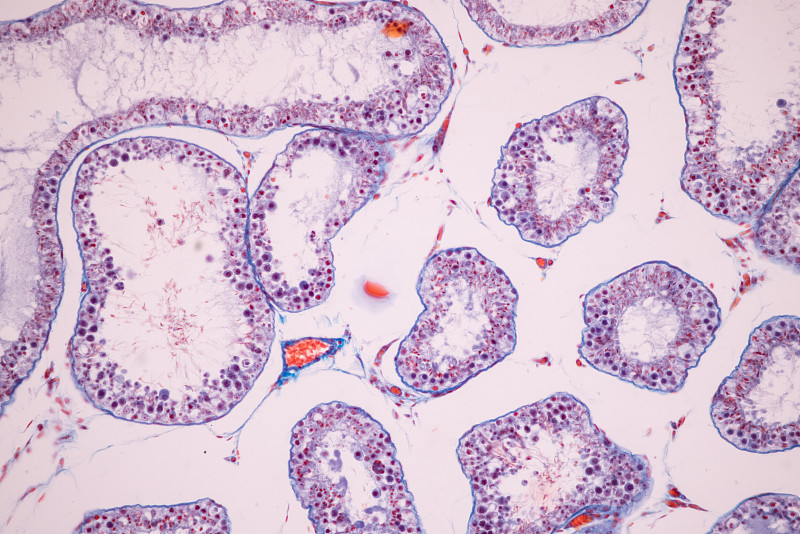

显微镜下的人类细胞详情

JPG